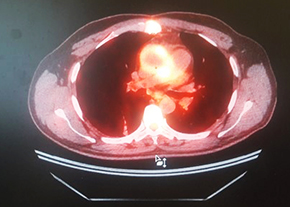

Рисунок. ПЭТ/КТ-картина протезного эндокардита аортального клапана.

ПЭТ с 18F-ФДГ: ПЭТ/КТ-картина в пользу протезного эндокардита аортального клапана.